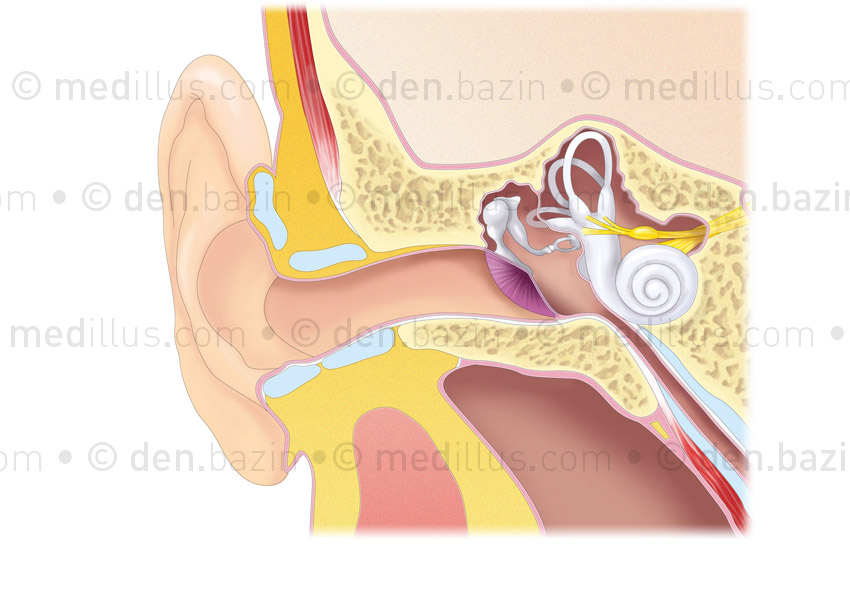

Anatomie de l'oreille